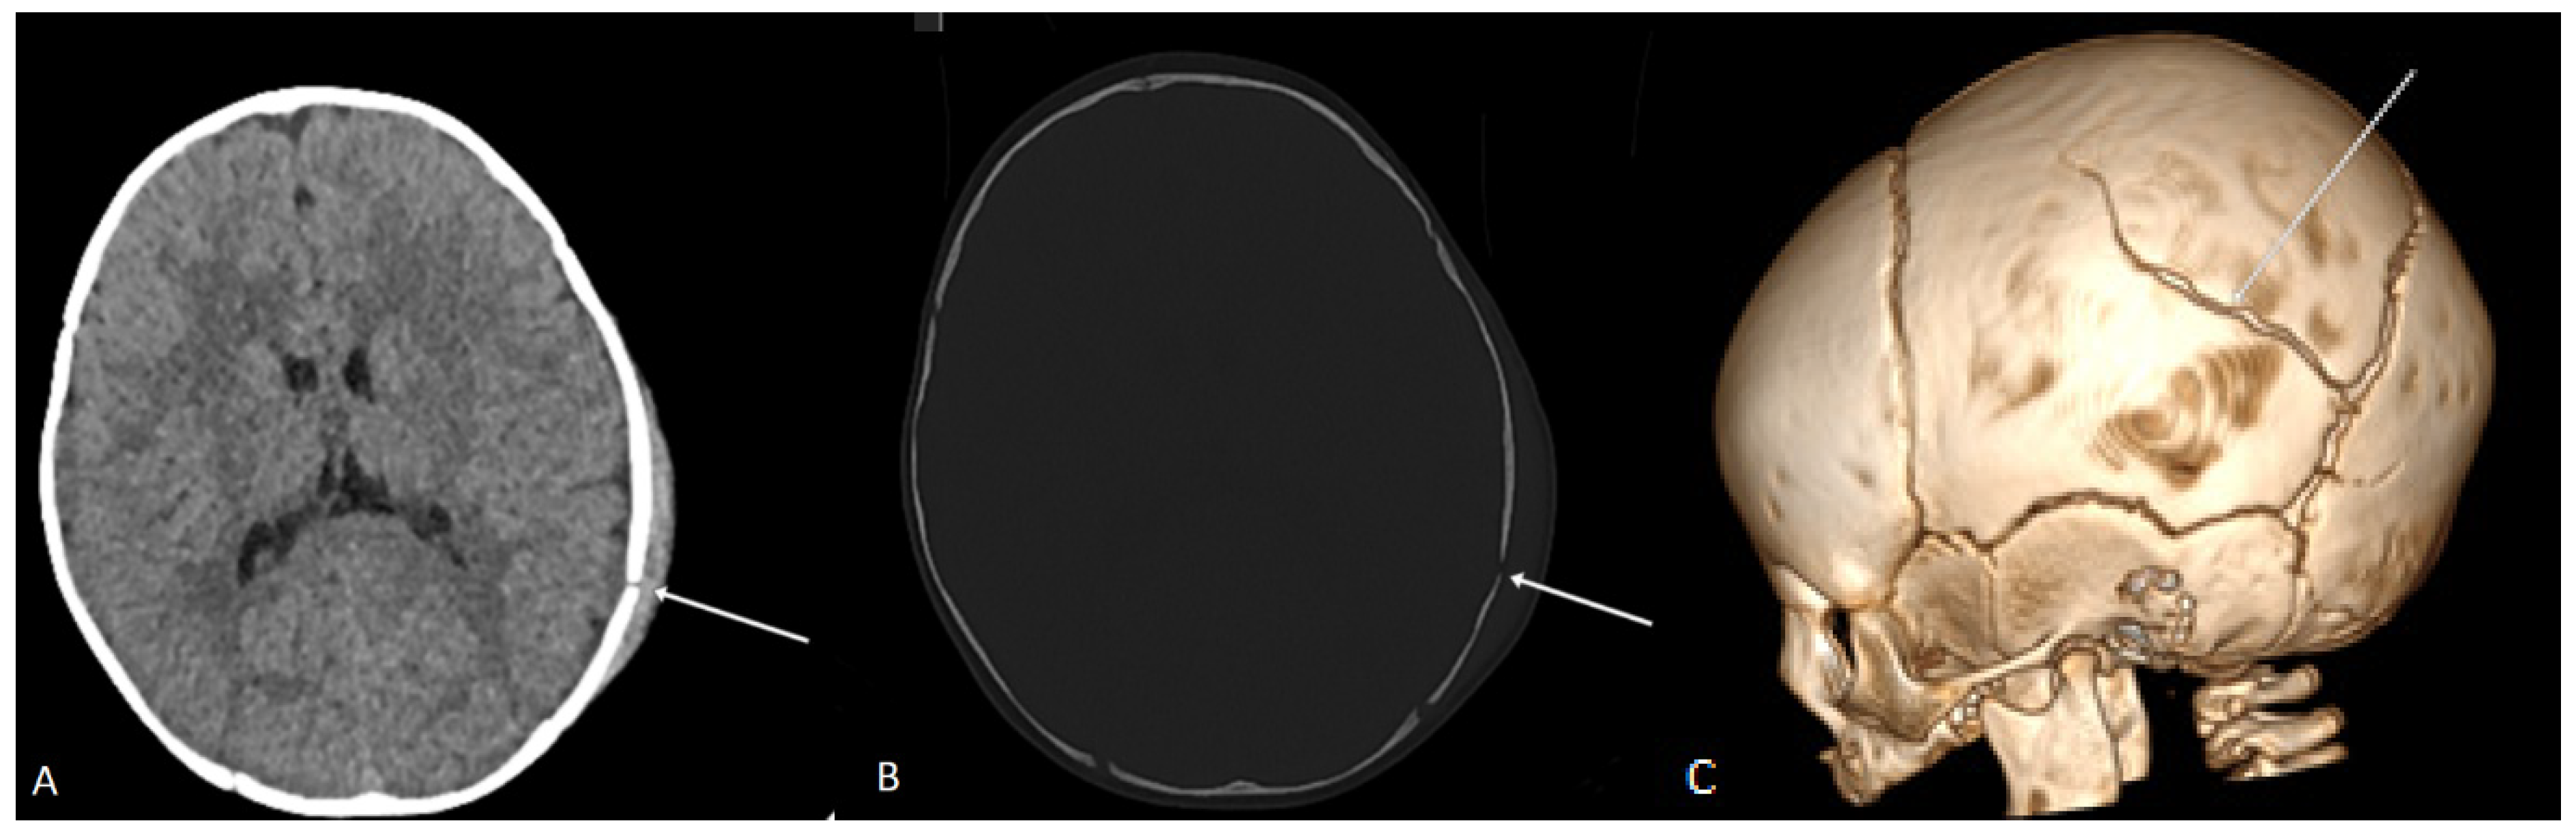

Skull fractures were present in 46% (103) of patients. Among these, 92.8% were linear fractures (Figure 1), 7.2% had fragmented fractures, and 9.8% presented with fracture dislocation. Brain edema was found in 7.6% of cases, intracranial hematoma in 13.8%, displacement of the midline structures in 0.9% and changes in the subarachnoid space in 11.2%. Additionally, changes in the ventricular system were noted in 8% of cases (Table 3).

Figure 1. Axial plane CT scan in the soft tissue window (A) and bone window (B) of a 5-month-old child, showing a linear fracture of the left parietal bone with soft tissue edema and a subcutaneous hematoma of the scalp. In the VRT reconstruction, an arrow indicates the communication of the linear fracture of the left parietal bone with the lambdoid suture (C).